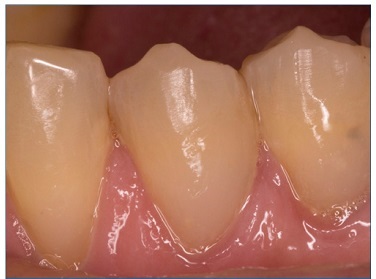

There were no dropouts in this study, so all patients were evaluated at baseline and at 6 months. Representative images of restorations are presented in Figures 1, 2, 3, 4, 5, and 6.

Figure 2 Photographs after 6 months of tooth 34’s restoration by the etch‑and‑rinse technique and tooth 45’s restoration by the self‑etch technique